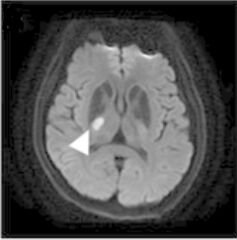

39.小洞梗塞性(lacunar infract)中風病患,呈現左側下肢無力,根據影像檢查(如下圖),其受損位置應為下列何者? (A)內囊後腳 (B)視丘 (C)大腦腳 (D)上小腦腳